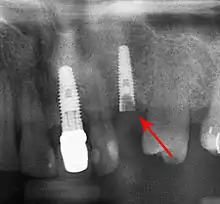

Bone loss (peri-implantitis) on implants over 7 years in a heavy smoker

Fixture show

Recession of the gingiva leads to exposure of the metal abutment under a dental crown.

Cement peri-implantitis

Dental cement under the gingiva causes peri-implantitis and implant failure.